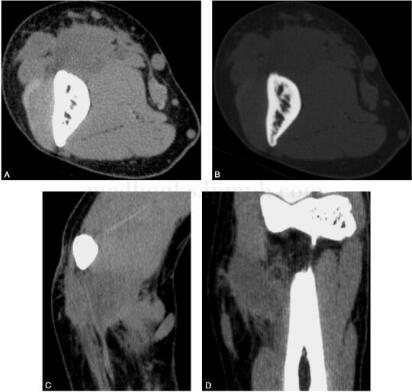

图2 CT:右肱骨下段邻近软组织内见直径约为2.2cm×1.8cm大小的软组织肿块影,边界不清,略低于肌肉密度,CT值约为36HU。邻近骨质未见异常

图3